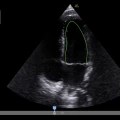

Ecografo POC - Venue GO

GE Venue Go è la versione intermedia della famiglia POC Venue.

Il modulo ecografico carrellato si può separare e usare come portatile. Ha monitor touch da 15,6″, imaging clinico chiaro e strumenti automatici basati su intelligenza artificiale per valutazioni rapide e supporto decisionale in ambienti critici, batterie con autonomia fino a 2 h e superficie facile da pulire per la gestione delle infezioni. È progettato per movimentarsi agilmente nel reparto, con gestione intelligente dei cavi, uso intuitivo e resistenza agli urti.